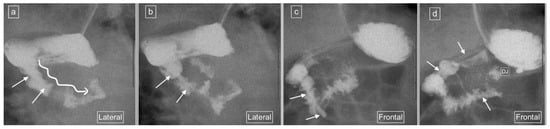

Figure 2.

(a–c): Representative images captured during an UGIS in a 3-month-old boy demonstrating duodenum redundum on the frontal and lateral views. (a) Frontal view demonstrates redundancy of the duodenal loop which instead of having a C-loop configuration now has a W-loop configuration (white line) and a normal position of the duodeno-jejunal flexure (immediately distal to the end of the arrowhead). (b) Early and (c) later lateral views captured prior to the frontal view in (a) demonstrate a descending staircase configuration of D1 and D2 oriented posteriorly, after which the duodenum ascends in the retroperitoneal position, leading up to the duodeno-jejunal flexure in the expected normal position at the same height as D1, before coursing anteriorly.

Figure 3.

(a–d): Representative images captured during an UGIS in a 49-day-old boy demonstrating duodenum redundum on the frontal and lateral views, with the order of images representing the order that the images were captured through multiple repositioning maneuvers. (a) Lateral view demonstrating the descending staircase sign oriented posteriorly from D1 and involving D2. (b) Frontal view demonstrating the W-loop configuration of duodenum redundum made up here by D2 and D3. (c) Repositioning in the lateral view demonstrates the posterior position of D3 inferiorly and that the ascending D4 remains posterior. (d) Return to the frontal position now demonstrates the contrast outlining the duodeno-jejunal flexure (DJ) just slightly inferior to D1 and to the left of the spine—considered within the normal range allowing for patient positioning.

Figure 4.

(a,b): Representative images captured during an UGIS in a 2-month-old boy demonstrating duodenum redundum on the lateral and frontal views. (a) Lateral view demonstrates a descending staircase configuration of D1 and D2 oriented posteriorly, after which the duodenum remains (D3) and ascends (D4) in the retroperitoneal position, leading towards the duodeno-jejunal junction (not shown here). (b) Frontal view demonstrates redundancy of the duodenal loop which, instead of having a C-loop configuration, has a W-loop configuration, made up of D2, D3 and D4 (white line) and a normal position of the duodeno-jejunal flexure (DJ).